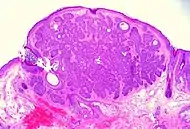

Nodular basal-cell carcinoma (also known as "classic basal-cell carcinoma") accounts for 50% of all BCC.[25] It most commonly occurs on the sun-exposed areas of the head and neck.[26]: 748 [27]: 646 Histopathology shows aggregates of basaloid cells with well-defined borders, showing a peripheral palisading of cells and one or more typical clefts.[25] Such clefts are caused by shrinkage of mucin during tissue fixation and staining.[28] Central necrosis with eosinophilic, granular features may be also present, as well as mucin. The heavy aggregates of mucin determine a cystic structure. Calcification may be also present, especially in long-standing lesions.[25] Mitotic activity is usually not so evident, but a high mitotic rate may be present in more aggressive lesions.[25] Adenoidal BCC can be classified as a variant of NBCC, characterized by basaloid cells with a reticulated configuration extending into the dermis.[25]

Cleft.